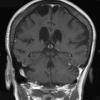

VASCULAR

Cavernous Angioma (10)